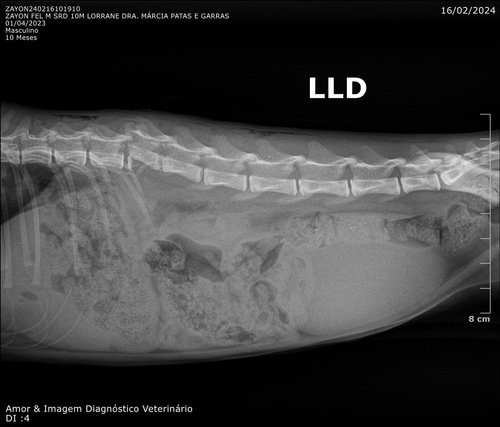

Olá, me chamo Ana Paula e criei essa vaquinha para este gato que resgatei das ruas, o qual chamei carinhosamente de Zayon. Não sabemos ao certo o que lhe aconteceu, o que sabemos é que Zayon está com uma fratura na coluna. Porém, por um milagre de Deus, ele responde a estímulos na perna, e consegue controlar o xixi, ou seja, a sua medula não foi afetada na fratura, o que torna de Zayon um verdadeiro milagre!

Levamos ele no veterinário, e agora ele precisa da sua ajuda para fazer uma cirurgia que pode tirar sua dor e possivelmente fazer com que ele volte a andar. O valor pedido corresponde ao valor da cirurgia, anestesia e dos dias em que ele precisará ficar internado.